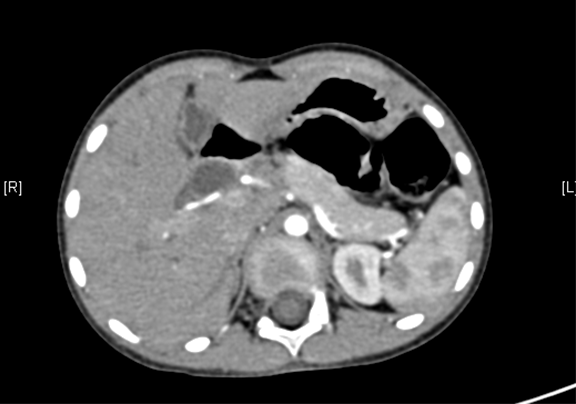

术前CT检查:

动脉期

静脉期

平衡期